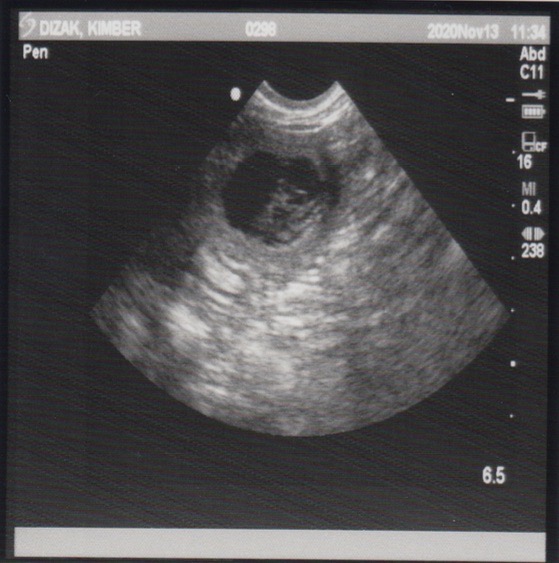

November 13, 2020 – Ultrasound

Since this was an artificial insemination and the success rate a bit lower than natural breedings, we wanted to have an ultrasound done to see if there are any little beings growing inside of Miss Kimber. Well, our repro vet confirmed this morning that Kimber is indeed pregnant!